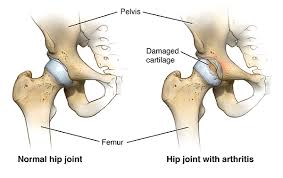

Patients with severe arthritis, avascular necrosis, or hip damage from injury may be considered for advanced hip replacement.